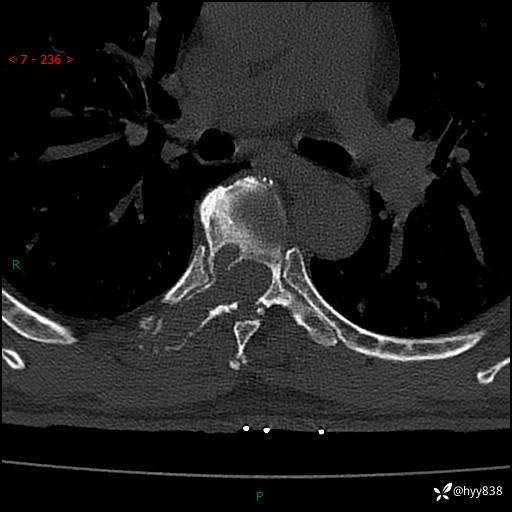

胸椎CT平扫(骨窗+软组织窗)